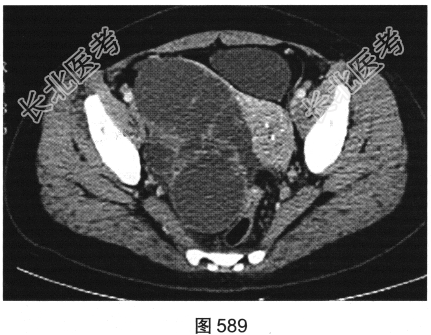

患者女性,38岁,因“间断性下腹部疼痛1周”入院。既往:否认肝炎、结核病史。查体:下腹部压痛。患者行腹部CT检查,见图582~图589。

- 多项选择题1.结合病史及影像学检查结果,可以考虑患者为以下哪些疾病( )

A、肝脏囊肿+附件囊腺瘤

B、肝脏转移瘤+附件囊腺癌

C、肝脏炎性假瘤+附件囊肿

D、肝脏炎性假瘤+输卵管积液

E、肝脏转移瘤+附件囊腺瘤

F、肝脏转移瘤+附件转移瘤